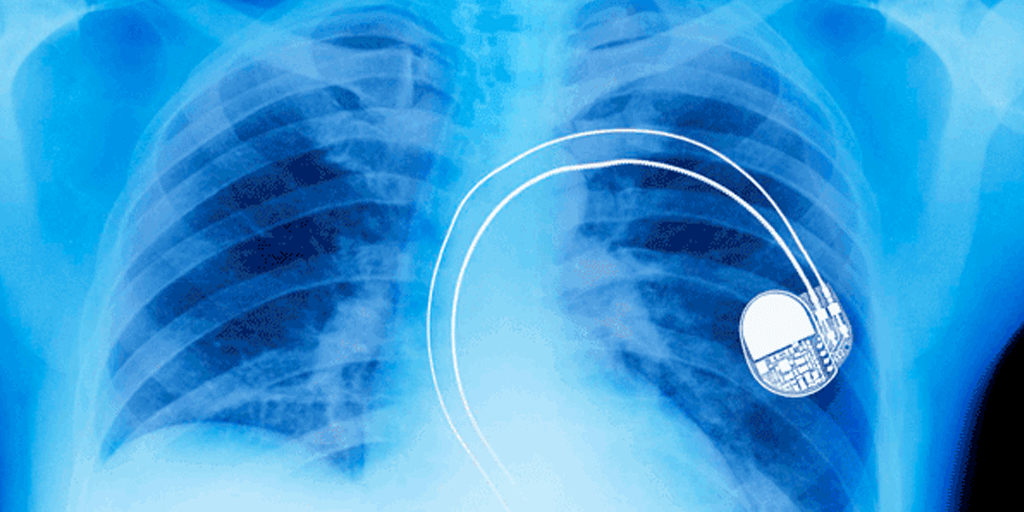

Pacemaker Placement GlobeHealer